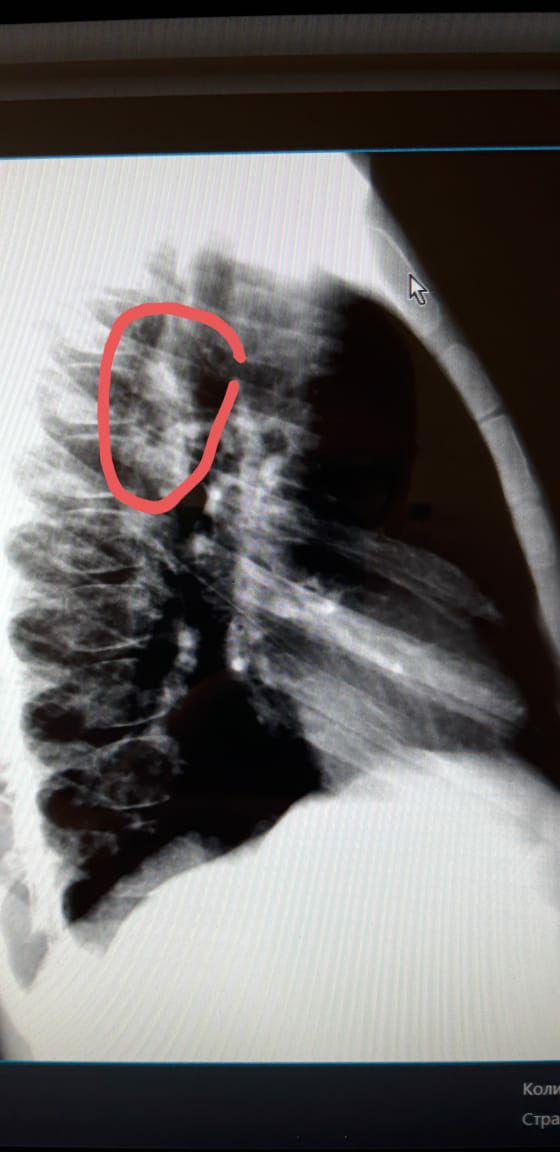

Здравствуйте ув. Коллеги! Посмотрите снимки ребенка мальчика 2016г. В крови от 5 июля-45 СОЭ. Неделю назад температурил. Сейчвс педиатр ставит ОРИ...Обследование... мы с Белой  Солт.решили что там с / долевая пневмония справа.....но никто кроме меня не видит овоидную тень  в С1-2?...я понимаю по этим снимкам трудно судить...но я сделала несколько с разной интенсивностью снимков... пожалуйста кто  что может посоветовать....мы решили пролечить и контроль...

Фото от 777